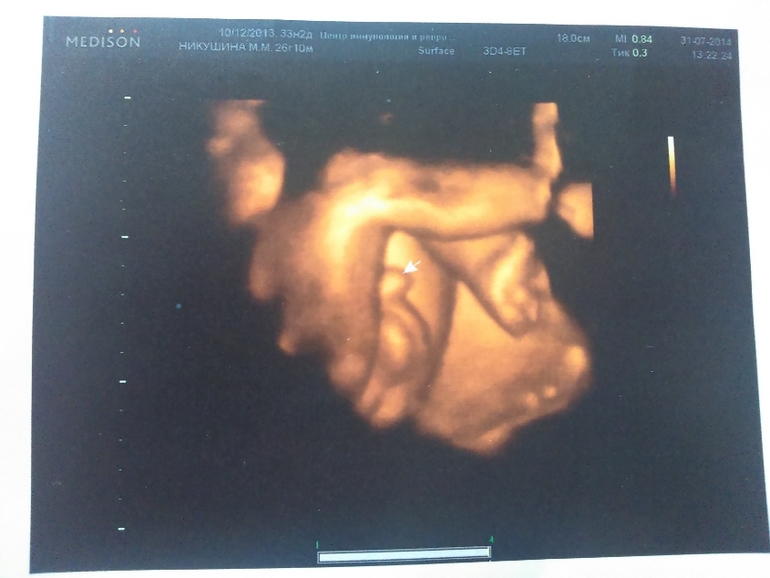

Лежит наш слоненок головой вниз, прижавшись к стенке матки носом, поэтому 3Д фотографии личика не очень вышли хорошо. зато причиндалы демонстрировал охотно)))

А сам сыночек такой классный)) хмурился, жмурился, плевался)) стопа уже 7 см

ну и пара фоточек (не очень лицо видно было, но разглядели папины щеки и губы и мой нос))))

ушко)

стопочка